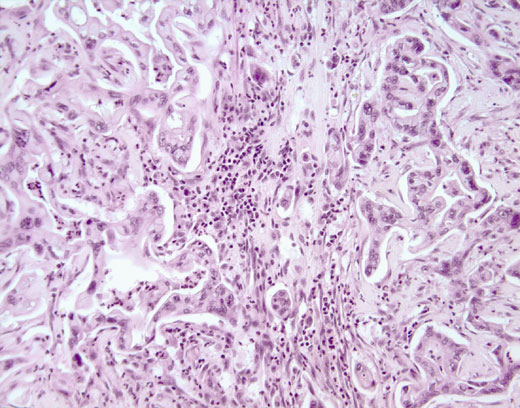

Cross-section #50 - 20X